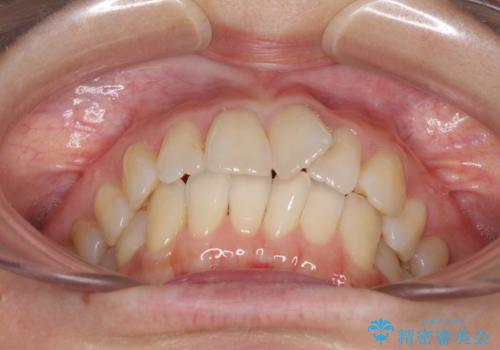

- 前歯の捻れと、それに伴う口元の突出感を気にして来院された患者様です。

早く治療を終えたいとのことで、ワイヤー装置による矯正治療を行うこととしました。

上顎前歯の叢生が解消されると出っ歯になることが分かっていたので、両側奥歯付近にアンカースクリューを入れ、出っ歯を改善するためのゴムかけを行いました。